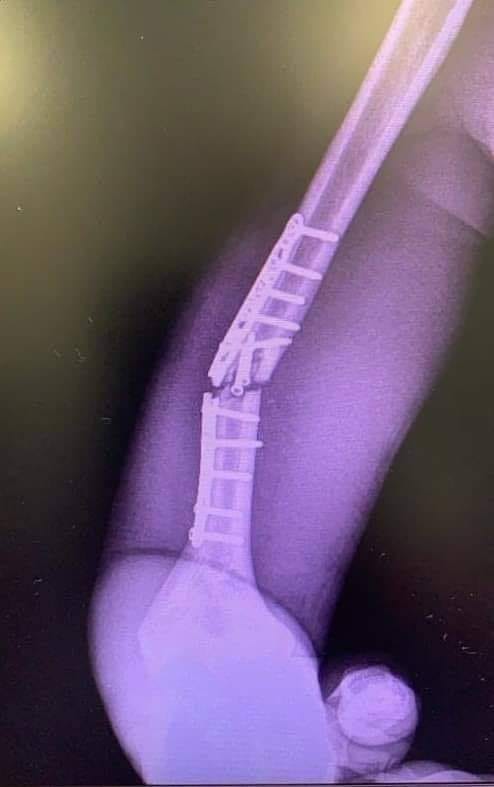

Marc Marquez目前在年度冠軍的排行榜上一分未得,對於追求衛冕冠軍的Marquez來說肯定是非常焦慮,前幾日他更在社群媒體上貼出自己進行重訓的影片,看得出Marc Marquez積極重返賽道的決心,但或許是太過求好心切,過度的訓練加上先前出戰安達盧西雅站累積的壓力,導致Marc Marquez右手肱骨的固定鈦板斷裂,不得不馬上進行第二次手術替換固定材料。

這次手術同樣由Dexeus大學醫院的Xavier Mir醫師執刀,Xavier Mir醫師表示Marc Marquez的手術相當成功,結束後Marc Marquez的恢復狀況也相當良好,但必須在醫院休養48個小時,這也讓人懷疑究竟Marc Marquez能否順利出賽本週末的捷克站。